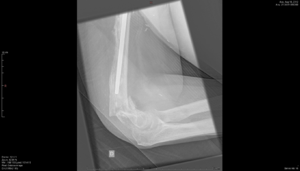

One month after implantation of a reverse shoulder arthroplasty for a proximal humeral fracture. The X-ray revealed a prosthetic dislocation. Electroneuromyography (ENMG) confirmed a severe axonotmesis of the axillary nerve.